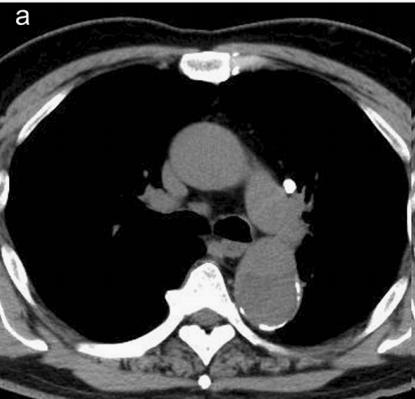

有些小伙伴开始焦急了: 鲁迅你别说了,我们家的CT分辨率低,平扫绝对看不出动脉夹层!

下图的胸部CT平扫,有什么致命的问题?

图15

血管壁钙化啊,老年人很常见啊,能说明个锤子!

注意,看下面,钙化在血管的里面,不是在管壁!难道是血液钙化了?血液钙化?什么鬼?

图16

这不是血液钙化,这是主动脉夹层导致的血管钙化内移!血液不会钙化,因为动脉夹层,导致钙化的内膜被压迫进入血管!

增强CT一看,就一清二楚了!